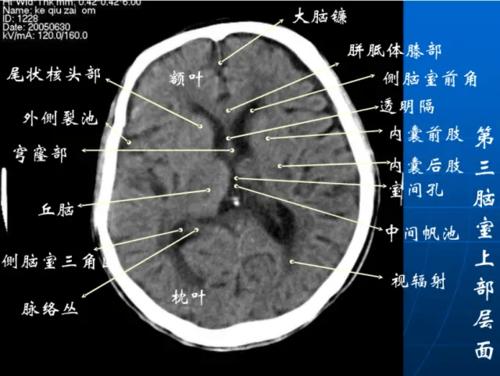

头部CT解剖

头部CT解剖,头部CT解剖

头颅ct断层解剖

影像医生必须掌握的头颅ct解剖与常见出血梗死判读

头颅ct影像解剖

头颅ct 解剖图谱,人手一份

正常头颅ctppt

头颅ct解剖

颅脑ct解剖